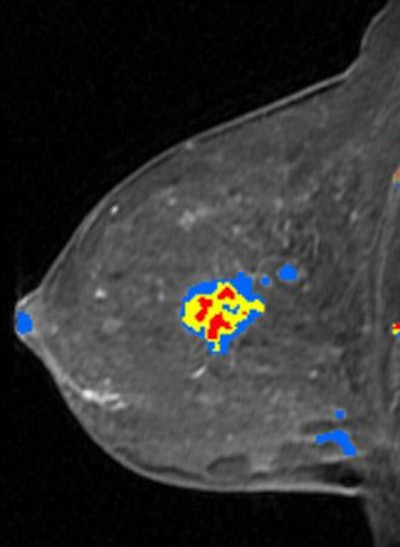

| Breast MRI advocates believe that CAD software saves time and makes images easier to interpret. Image courtesy of Confirma. |

But analyzing breast MRI exams can be a time-consuming process. While expert mammographers can analyze dozens of screening mammograms in an hour, a single breast MRI study has thousands of images and can take 30 minutes or more to review. Several companies have developed CAD software to help automate and speed up the process, including CAD Sciences of White Plains, NY; Confirma of Bellevue, WA; and Invivo of Orlando, FL.

"Breast MRI CAD makes me more efficient and also more accurate," Middleton said. "The CAD provides information that can automatically be gleaned from the data and presented to a radiologist in an organized way."

Dr. Michael Linver of X-Ray Associates of New Mexico in Albuquerque said that it's a contradiction for health insurance companies to pay for mammography CAD, but to deny payment for breast MRI CAD. The utility of CAD for conventional screening mammography has been well established in detecting early breast cancers, he noted. While suspicious lesions are visible with breast MRI, CAD software helps physicians interpret breast MRI studies with more confidence in less time.